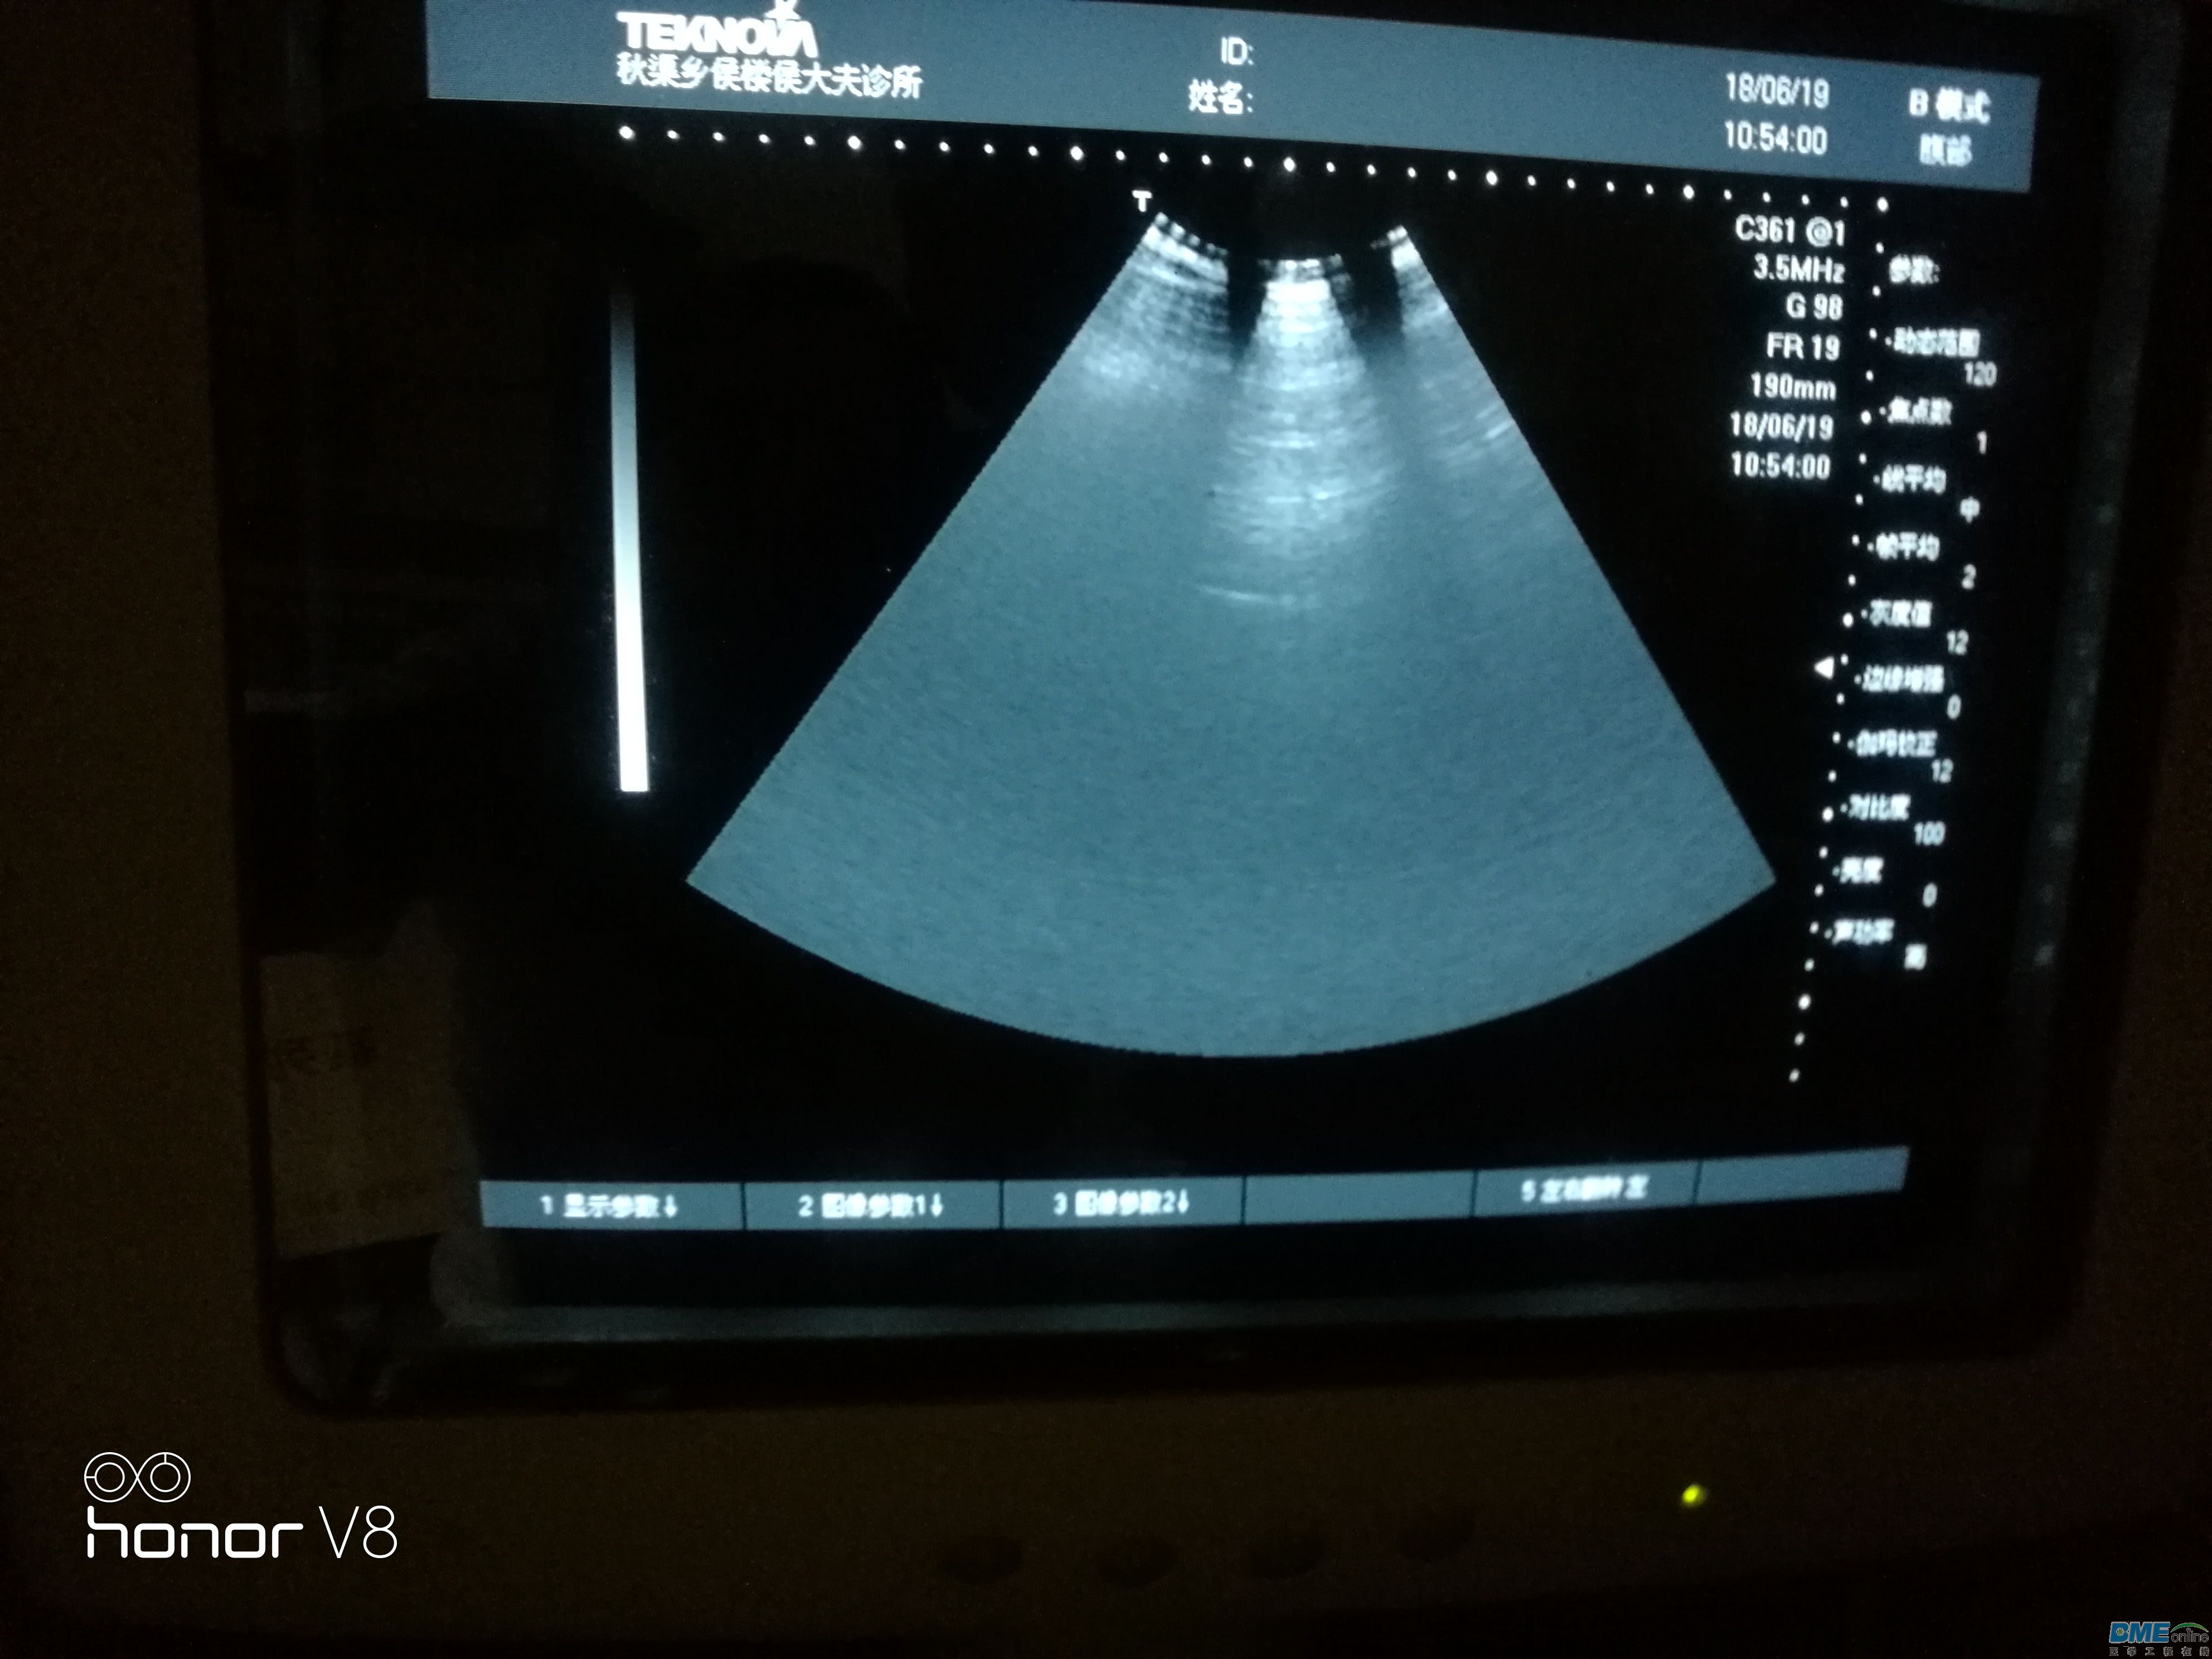

今天接收一台天惠华TH-200的B超级,问题是扇形区域里图像变小,如图扇形区域里只有上部分有图像,拔下探头图像不变。

,下面图是接入探头后直接测试腹部的图片,图上可以看出隐隐约约的影像探头接入后探测腹部扇形区域能有阴影的影像,开机拔去探头扇形区域只有一点点影像!求教维修思路